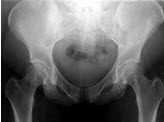

140、单项选择题

男,根据其正常骨盆影像图像,判断其最可能的年龄()

A.1岁左右

B.4岁左右

C.7岁左右

D.10岁左右

E.13岁左右

203、单项选择题

A.68岁左右

B.58岁左右

C.18岁左右

D.48岁左右

E.28岁左右

204、单项选择题 骨肉瘤主要转移途径为()